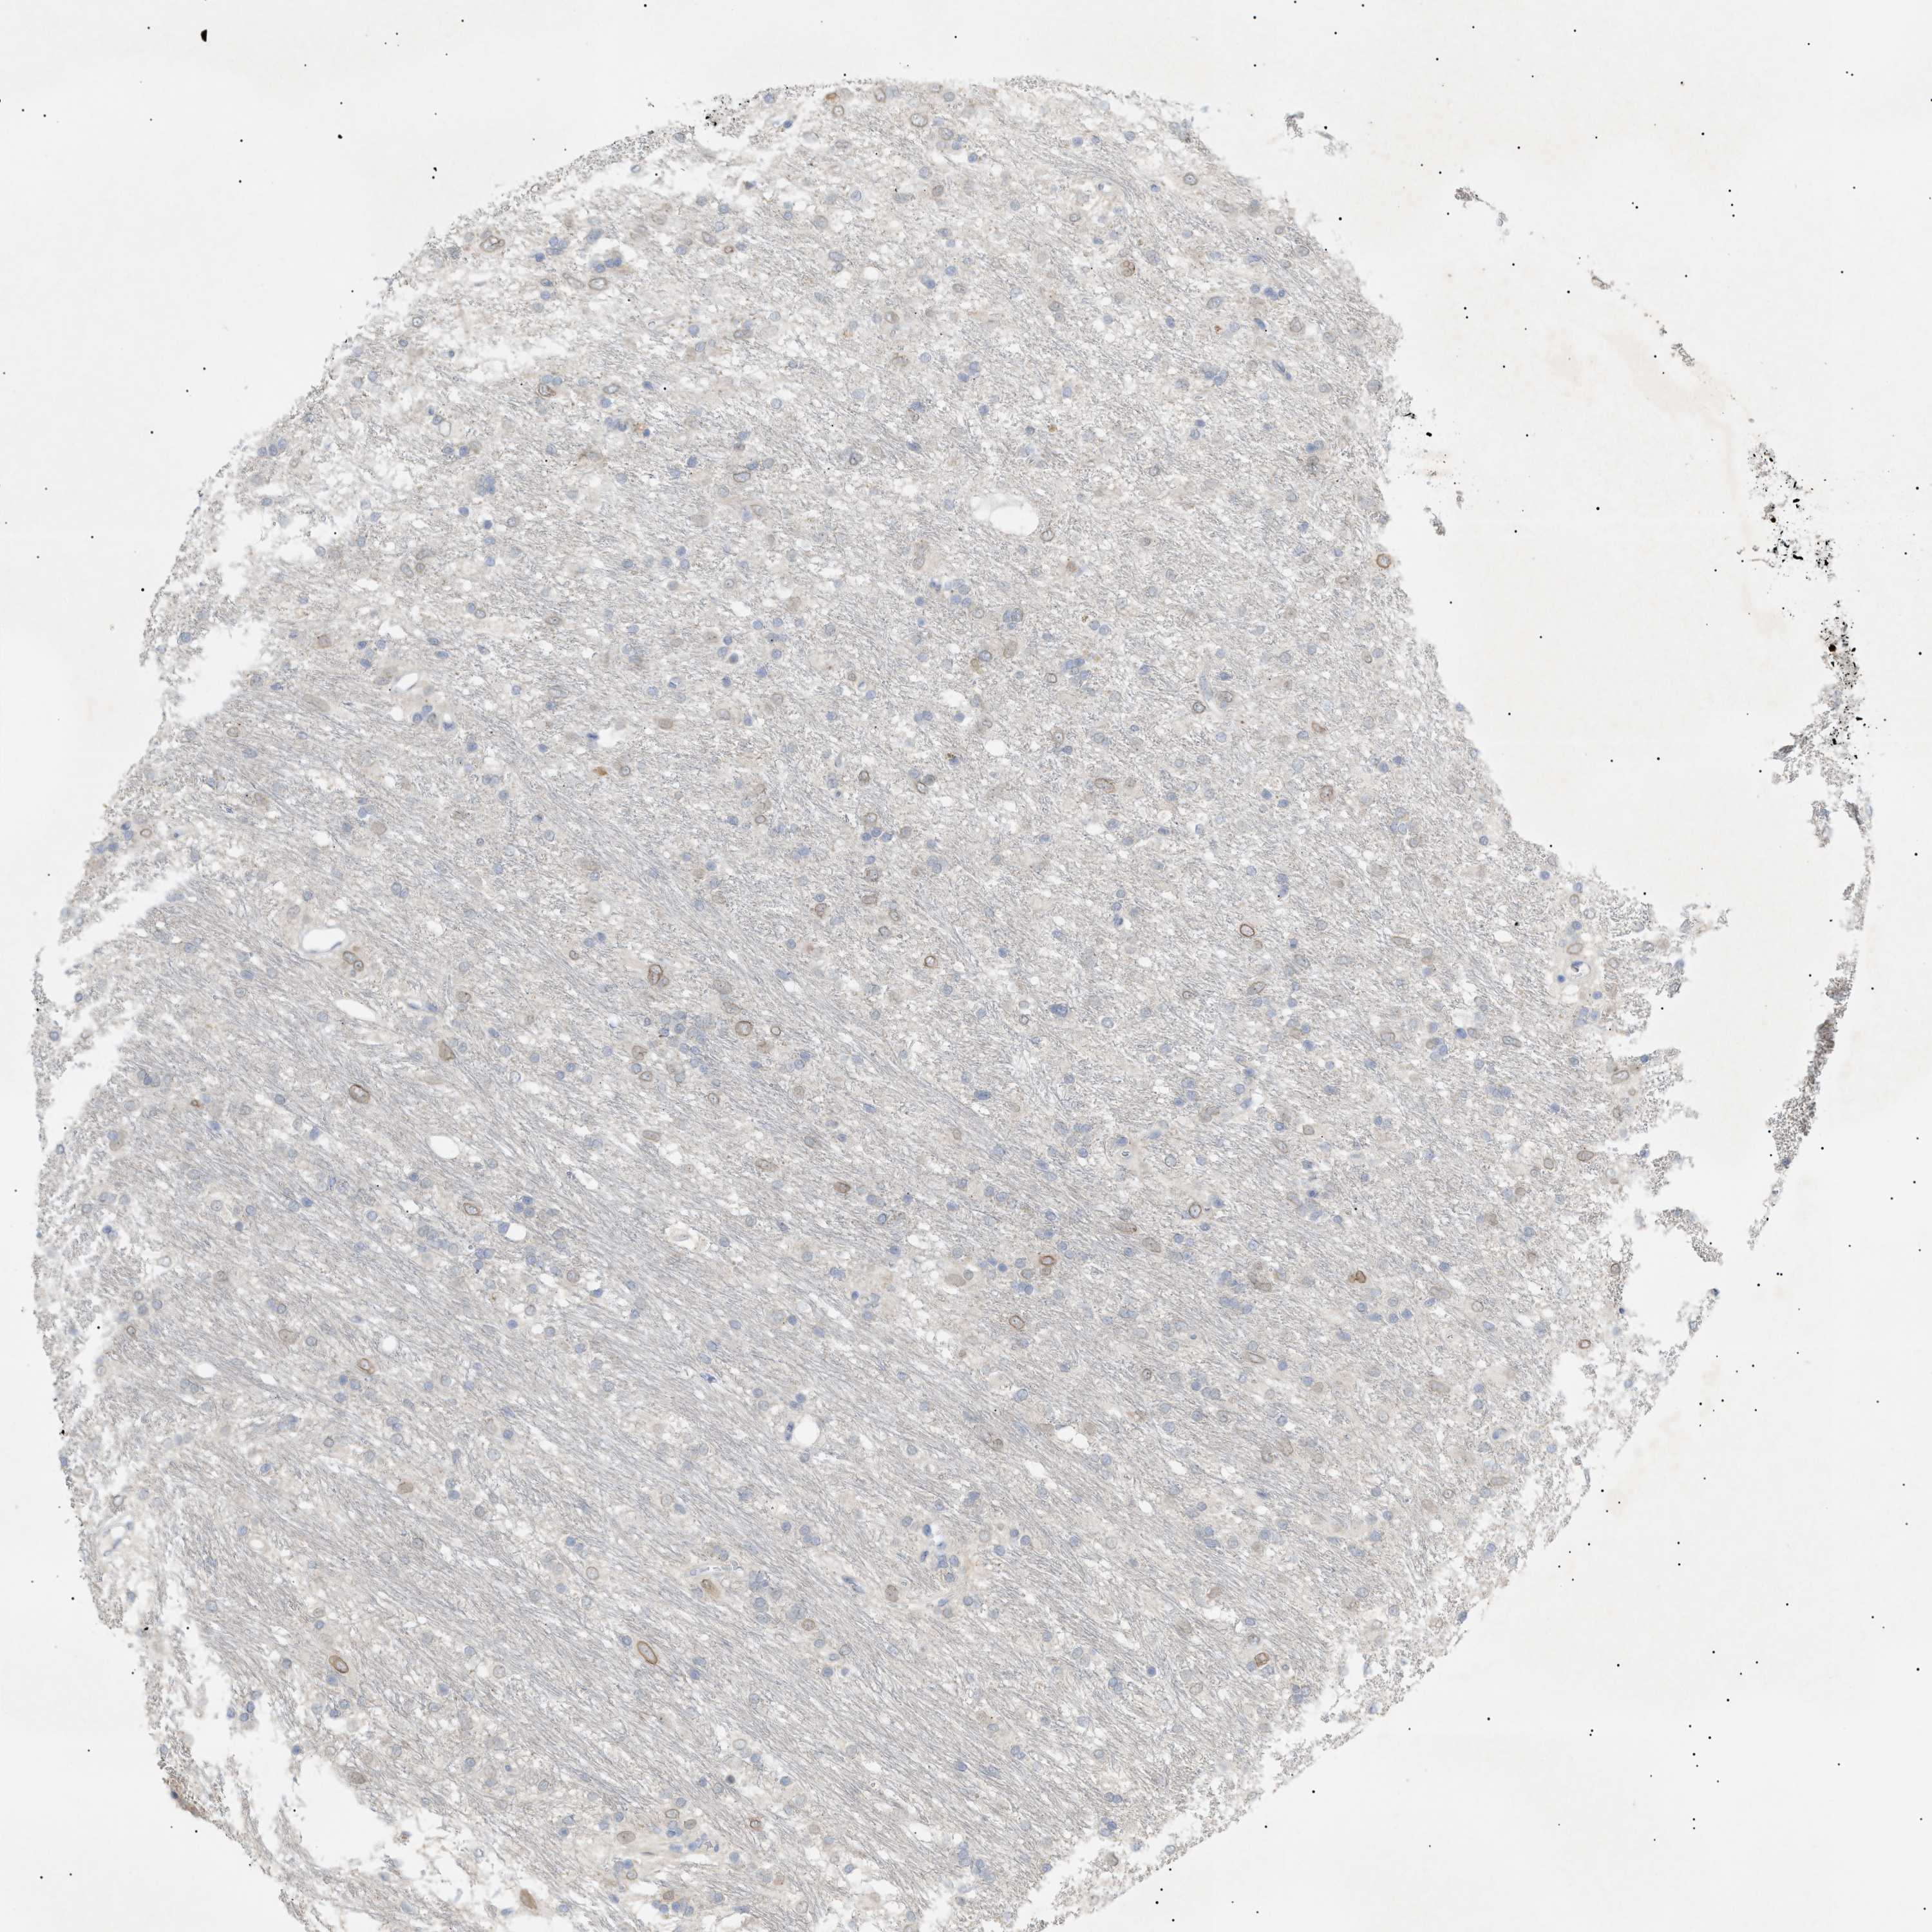

GLIOMA - Protein expressioni

A mouse-over function shows sample information and annotation data. Click on an image to view it in a full screen mode. Samples can be filtered based on level of antibody staining by selecting one or several of the following categories: high, medium, low and not detected. The assay and annotation is described here.

Note that samples used for immunohistochemistry by the Human Protein Atlas do not correspond to samples in the TCGA dataset.

Antibody stainingi

Antibody staining in the annotated cell types in the current human tissue is reported as not detected, low, medium, or high, based on conventional immunohistochemistry profiling in selected tissues. This score is based on the combination of the staining intensity and fraction of stained cells.

Each image is clickable and will lead to virtual microscopy that enables deeper exploration of all samples and also displays staining intensity scores, fraction scores and subcellular localization as well as patient and tissue information for each sample.

Antibody HPA015064

Antibody HPA071684

Glioma, malignant, High grade

Glioma, malignant, Low grade